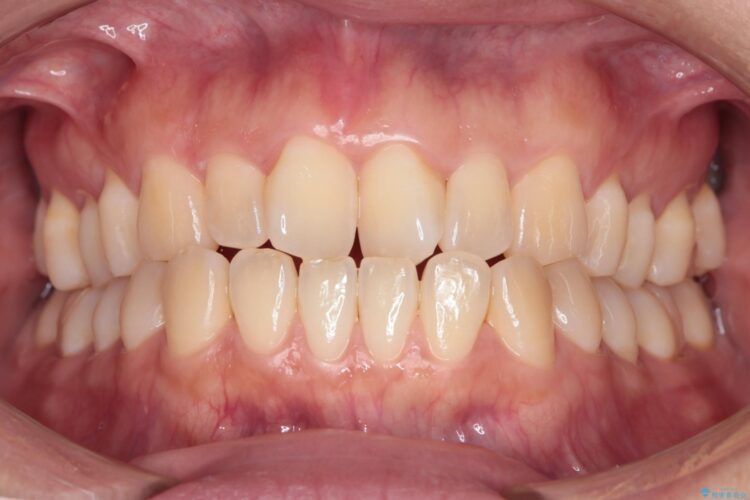

上の前歯のねじれが気になるとご来院された患者様です。

前歯の捻れとがたつきを改善するために、IPR(歯と歯の間を削る処置)と歯列拡大をすることで歯並びを整えていく治療計画を立てました。

治療後について

かみ合わせを整えるためにゴム掛けも併用して治療を行いました。